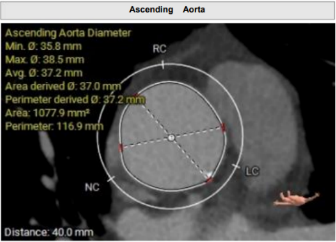

术前影像学评估 (3mensio)

瓣环及其他基本平面测量

术前影像学评估(Tavigator™AI术前辅助决策平台)